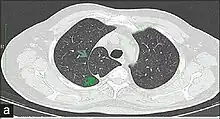

In human anatomy, an azygos lobe is a normal anatomical variation of the upper lobe of the right lung.[1] It is seen in 0.3% of the population.[2] Embryologically, it arises from an anomalous lateral course of the azygos vein,[3] in a pleural septum within the apical segment of the right upper lobe or in other words an azygos lobe is formed when the right posterior cardinal vein, one of the precursors of the azygos vein, fails to migrate over the apex of the lung and penetrates it instead, carrying along two pleural layers as the azygous fissure, that invaginates into the upper portion of the right upper lobe.[1]

An azygos lobe is usually an incidental finding on chest x-ray or CT scan. It is asymptomatic and not associated with any morbidity.[4][5] However, it can cause technical problems in thoracoscopic procedures.[6] The presence of the azygos lobe could alter the normal location of the superior vena cava or may be associated with other anomalies, including esophageal atresia or intrapulmonary right brachiocephalic veins.[7]